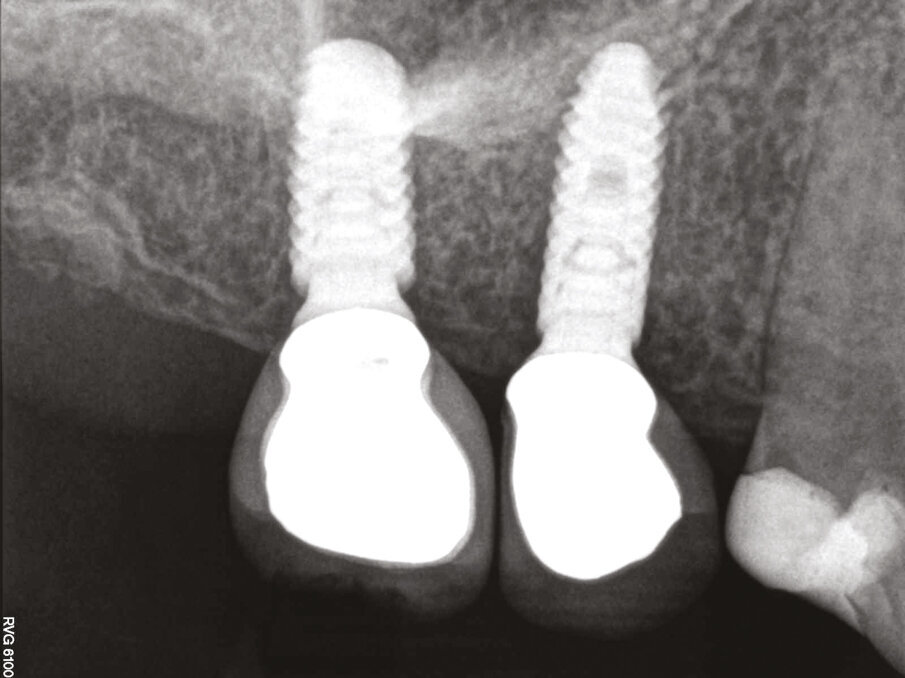

Fig.21: 1 year post x-ray showing bone formation over the top of the Axiom REG implants.

Figs.22-24: Final CT reconstructions and Pan xray.